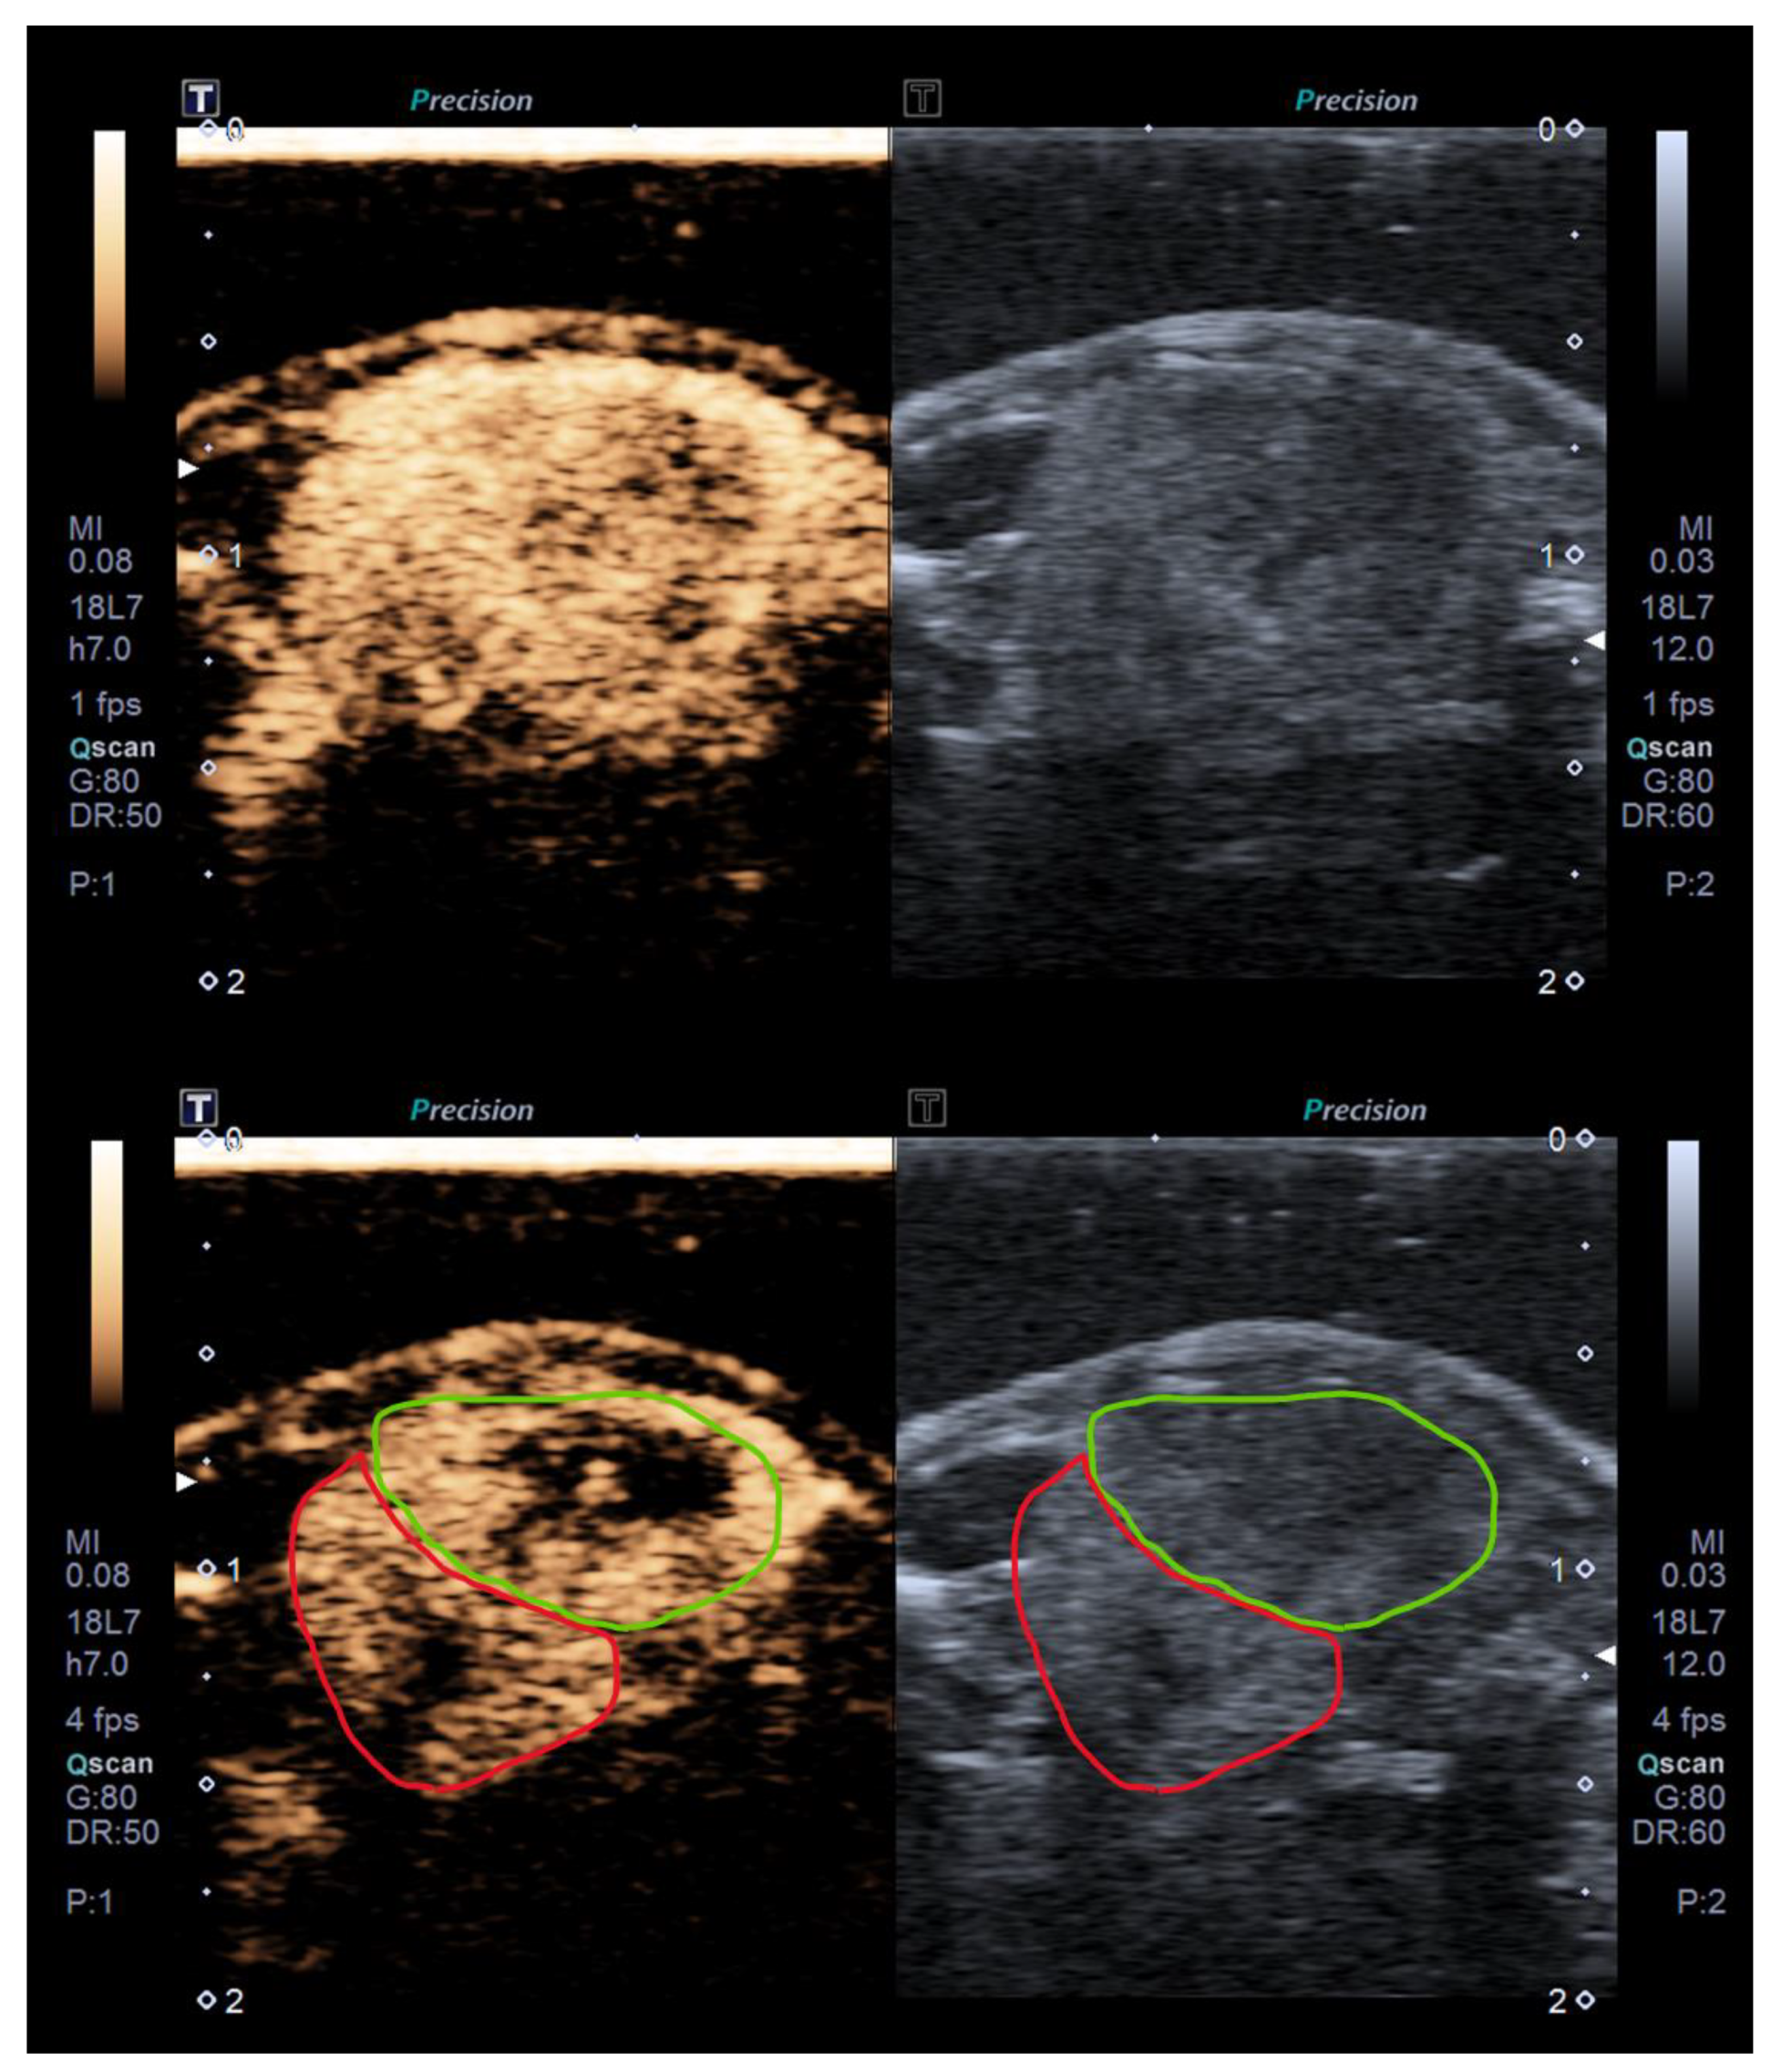

4.5. Ultrasound Molecular Imaging